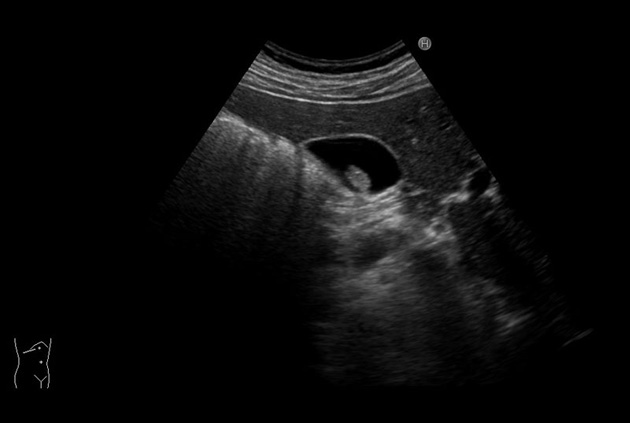

Contrast Harmonic Imaging (CHI)

Contrast-specific software is supported for use with contrast agents used with acoustic pressures from low to mid Ml. This is compatible with various transducers.